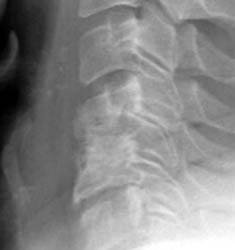

61 y.o male, s/p c4-5 discectomy and interbody fusion for myelopathy.

Initial post-operative films show bone graft intact, with mildly

prominent pervertebral soft tissues, as expected in the immediate post-operative

period. |